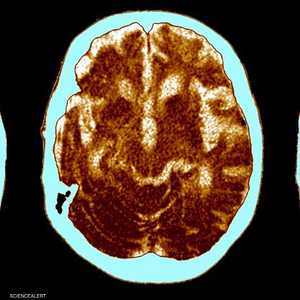

تزداد الأنباء التي تتناول علاجات جديدة لمرض ألزهايمر، إلا أن باحثين يرون أن أدوية هذا المرض حتى الآن محدودة الفعالية وذات آثار جانبية خطيرة برغم الضجة الإعلامية المصاحبة لها بحسب ما نشر موقع أكسيوس.

ويعتقد العلماء أن بروتين الأميلويد يتحلل ليعطي مواد تتراكم بكثرة في أنسجة الدماغ لدى مرضى ألزهايمر، وتدعى بيتا أميلويد.

وصوتت لجنة استشارية تابعة لإدارة الغذاء والدواء بالإجماع في وقت سابق من هذا الشهر لصالح عقار دونانيماب، وخلصت إلى أن فوائده تفوق مخاطره، حيث دعت الإدارة في وقت سابق إلى مراجعة الدواء بعد أن عانى بعض المرضى المسجلين في تجربة سريرية من تورم في المخ ونزيف وأحداث سلبية أخرى.